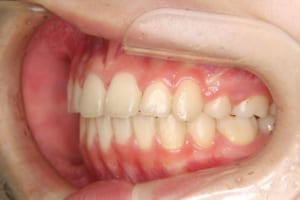

治療後

| その他/備考 | 上の犬歯が生えるためのスペースが全くない状態でした。放置すると重度の八重歯になることが想定されるケースです。 今回はあごの成長も利用しながら治療をするために、早めに後期治療(大人の矯正治療)に移行しました。 治療後レントゲン写真を見たところ、上顎前歯に若干の歯根吸収を認めました。 |